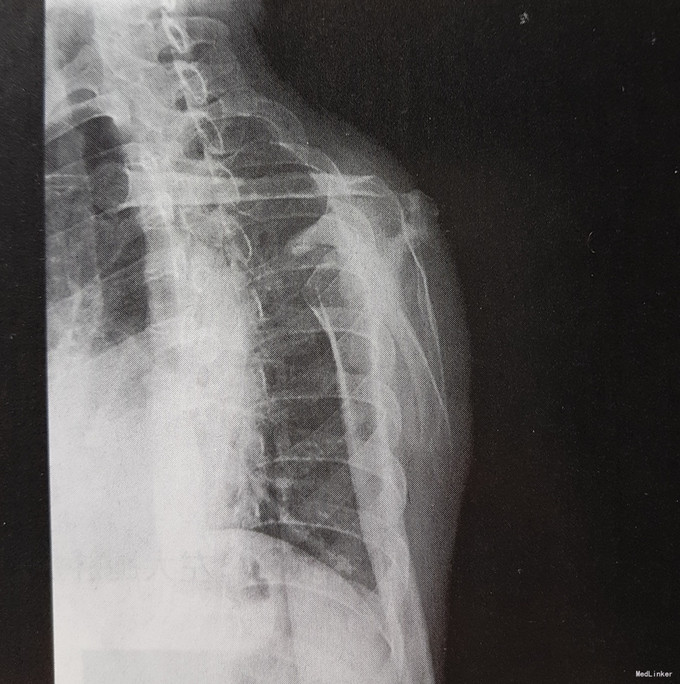

患者男,45岁,右肩疼痛3个月,无外伤及发烧史。患者3月前无明显诱因出现右肩疼痛,疼痛叫剧烈,服用药物及理疗不能缓解,休息时疼痛无明显减轻,为求诊治先来我院。

查体示局部压痛,皮温稍高,不红。生命体征平稳,心肺腹无明显异常。 实验室检查:AKP 180U/L 影像学检查如下

诊断:右肩胛骨占位 治疗:手术治疗 病理:可见形态、大小一致的瘤细胞,诊断为尤文肉瘤。

本例为发生于肩胛骨的尤文肉瘤,X线表现为局部骨质结构模糊,反应性增生,密度增高,具有部分扁骨尤文肉瘤的特点,但发病年龄不典型,诊断有一定困难,鉴别诊断需要考虑软骨肉瘤和成骨转移。成人不规则骨发生的恶性病变最常见的为软骨肉瘤,病灶内出现环形的软骨钙化是诊断最重要的线索。